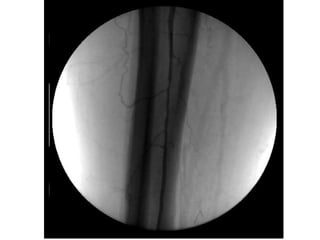

ISQUÉMIA CRÍTICA TRATAMENTO - Revascularização Cirurgia convencional Cirurgia endovascular - Proximal - Distal - Multisegmentar

ISQUÉMIA CRÍTICA TRATAMENTO- Revascularização Cirurgia convencional Cirurgia endovascular - Proximal - Distal - Multisegmentar